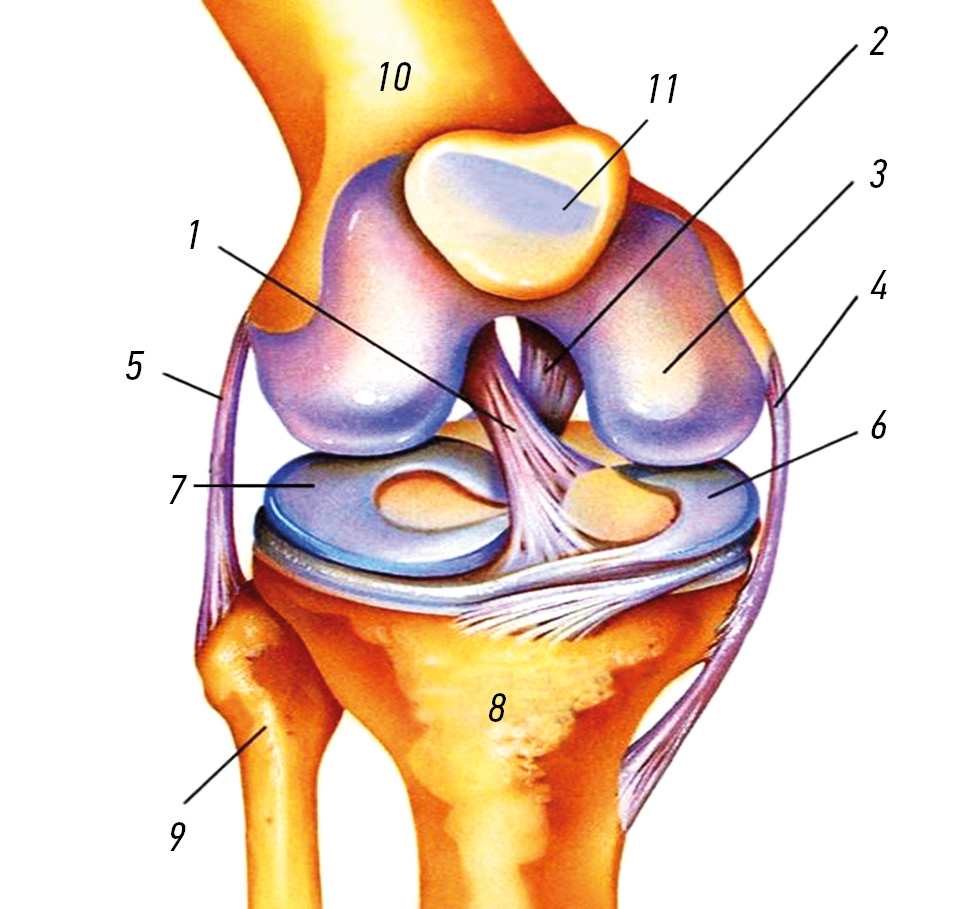

The knee joint menisci are paired, and as the name implies, they are crescent-shaped (Fig. 1) and located between the tibial plateau and femoral condyles. The meniscus is represented by fibrous cartilage. The shape of the menisci fits perfectly between the concave surface of the femoral condyles and tibial plateau, which has a flatter surface [30]. The medial and lateral menisci have different sizes, as the lateral menisci are 32.4–35.7 mm long and 26.6–29.3 mm wide, whereas the medial menisci are 40.5–45.5 long and 27 mm wide [31, 32]. Although both menisci are wedge- and crescent-shaped, the lateral menisci have various sizes, shapes, thicknesses, and degrees of mobility than the medial ones [27, 33].

Fig. 1. Knee joint structure: 1 — anterior cruciate ligament; 2 — posterior cruciate ligament; 3 — articular cartilage; 4 — internal lateral ligament; 5 — external lateral ligament; 6 — medial meniscus; 7 — lateral meniscus; 8 — tibia; 9 — fibula; 10 — femur; 11 — patella.